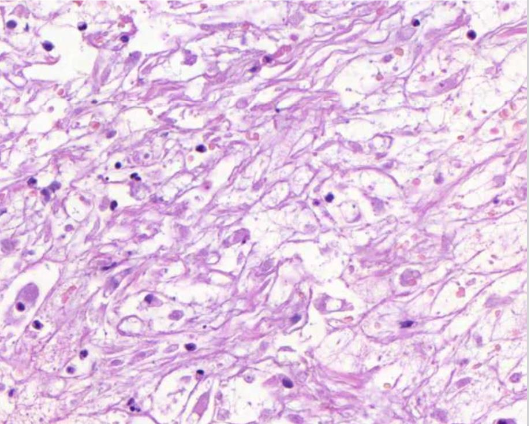

koagulaationekroosia

mitä nähdään tuumorin alueella? (vinkki: liposarkooma)

Liposarkooma

päättele kuvan avulla, mikä tauti on kyseessä?